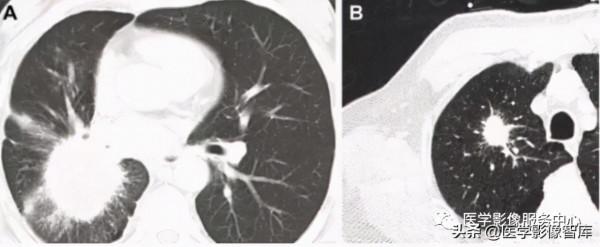

圖10. 放射冠徵 A和B顯示肺結節或腫塊邊緣多發不規則針狀、⽑刺狀改變

放射冠徵:放射冠徵亦稱⽇射徵,指單發的肺結節或腫塊(圖10A、10B),邊緣不規則呈針狀、⽑刺狀,周圍⾎管扭曲,更加形象表述了腫塊或結節的邊緣特點,提示是肺部惡性腫瘤。Shine提到“放射冠徵”應與結節病中的星系徵相鑑別,結節病中的星系徵是指胸部顯示的微⼩衛星結節,肺結節的外圍,呈星系狀,傾向於良性病變。

圖11. 星系徵 CT所⻅右肺上中央緻密的⼤結節和外圍微⼩的衛星結節類似於星系團

星系徵:星系徵⼜稱結節狀星系,指結節病中可⻅的肺實質結節及多個較⼩的間質結節組成,中央緻密的⼤結節和外圍微⼩的衛星結節類似於星系團。CT掃描的獨特之處在於 顯示結節邊緣有⽆數的⼩結節(圖11)。在進⾏性團塊狀纖維化和活動性肺結核中也可⻅此 徵象。衛星結節必須與典型的惡性肺結節相鑑別。結節病可引起雙側肺⻔淋巴結腫⼤,伴或不伴縱隔淋巴結腫⼤,與此相反,⼴泛的縱隔和雙側肺⻔淋巴結病在⾮⼩細胞肺癌中少⻅,尤其是在⼩於3cm的病變中。肺⻔和縱隔淋巴結內的鈣化也有利於結節病,在未經治療的惡性腫瘤中少⻅。